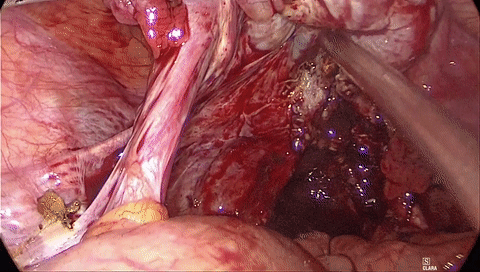

在创面广泛、持续渗血需要暴露时,吸引器头端迅速划过创面同时吸引,即为「扫吸」,可迅速暴露出血点,方便止血。

另外在手术出现出血的时候,可用吸引器头顶在出血点附近,减少出血量,并用合适的力量吸引,保持创面清洁,为下一步处理创造条件。控制出血时需要以顶为主,而尽量少用吸,特别不能对着出血点吸引。否则,虽然看着创面干净,但出血量反而更大。